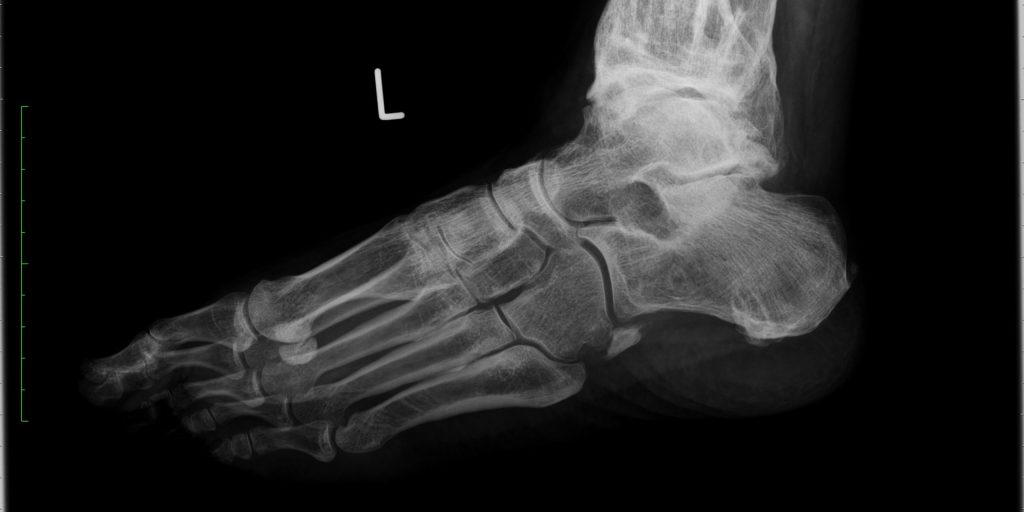

In der klinischen Untersuchung zeigte sich ein deutlich verplumtes und weichteilgeschwollenes linkes Sprunggelenk und die Beweglichkeit war im Vergleich zur gesunden Gegenseite deutlich eingeschränkt. Durch eine umfangreiche radiologische Diagnostik konnte des Ausmaß der posttraumatischen Arthrose verdeutlicht werden und die Indikation zur operativen Versorgung gestellt werden. Der Patient wurde mit einer Sprunggelenksendoprothese chirurgisch versorgt, um die Beweglichkeit und Schmerzfreiheit wiederherzustellen.